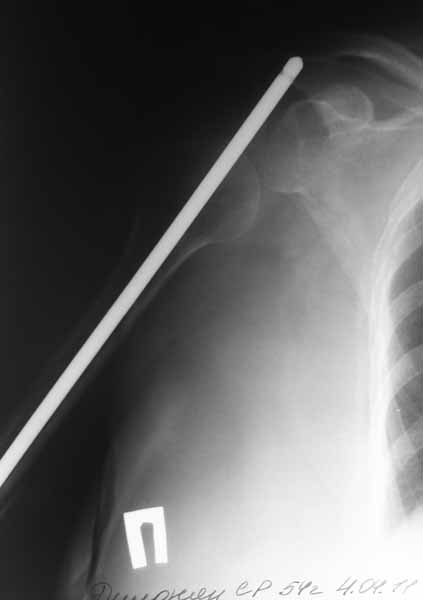

Доброго времени суток уважаемые коллеги.Представляю вашему вниманию пациентку 54 лет.Из анамнеза: травма в сентябре 2010 года в результате падения. В ЦРБ по м/ж выполнена открытая репозиция, синтез штифтом Кюнчера и проволочным серкляжами.

Рана заживала первично.Такая исходная длина штифта разъяснена пациентке как "непринципиальный" момент в общем процессе лечения. Гипсовая иммобилизация 2 месяца. По снятию гипсовой повязки пациентка отметила резкое снижение объема движений в плечевом суставе. Активное длительное ЛФК без эффекта.

Спустя 6 месяцев после операции пациентка госпитализирована к нам в клинику. После выполнения контрольных рентгенограмм помимо атрофичного ложного сустава н\3 плечевой кости был диагностирован нижний вывих головки плечевой кости.